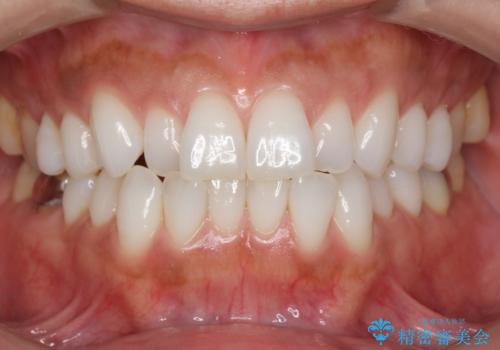

30代女性 前歯のがたつき

- 30代女性

- 前歯のがたつきを主訴に来院。

右下の奥の銀歯も治療しています。

下の前歯を下げるため、IPR(歯をわずかに削る処置)を行っています。